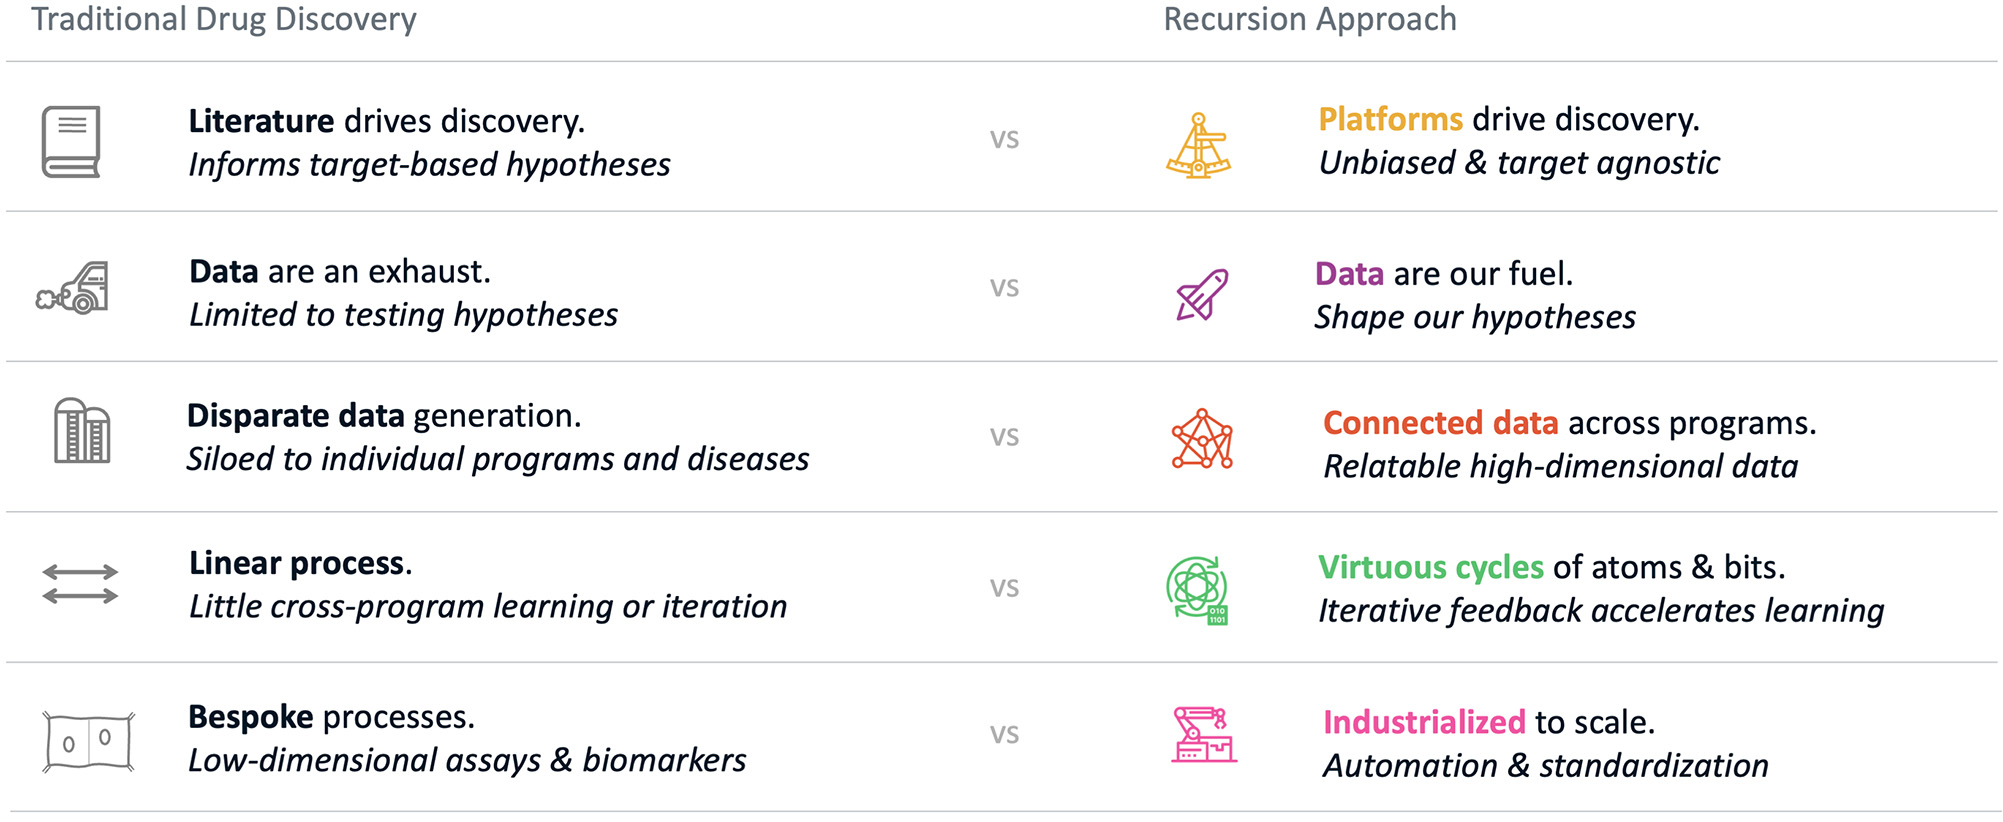

Despite significant investment and brilliant scientists, these metrics point to the need to evolve a more efficient drug discovery process and explore new tools. Traditional drug discovery relies on basic research discoveries from the scientific community to elucidate disease-relevant pathways and targets to interrogate. Coupled with biology’s incredible complexity, this approach has forced the industry to rely on reductionist hypotheses of the critical drivers of complex diseases, which can create a ‘herd mentality’ as multiple parties chase a limited number of therapeutic targets. The situation has been exacerbated by human bias (e.g., confirmation bias and sunk-cost fallacy). Accentuating this problem, the sequential nature of current drug discovery activities and the challenges with aggregation and relatability of data across projects, teams and departments lead to frequent replication of work and long timelines to discharge the scientific risk of such hypotheses. Despite decades of accumulated knowledge, the result is that drug discovery has unintentionally created hurdles for innovation.

Figure 6. Recursion’s approach to drug discovery. We utilize our Founding Principles on the right to build datasets which are scalable, reliable and relatable in order to elucidate novel biological and chemical insights and industrialize the drug discovery process.